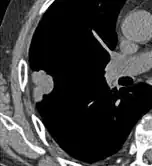

FDG-PET study of a 71-year-old woman with a solitary pulmonary nodule (thin arrow) in the left lower lobe near the heart. The scan also revealed abnormal increased activity at the gastro-esophageal junction (thick arrow). The final diagnosis was non-Hodgkin lymphoma at both sites.

If there is an intermediate risk of malignancy, further imaging with positron emission tomography (PET scan) is appropriate (if available). It can be done simultaneously as a CT scan in the form of PET-CT. Around 95% of patients with a malignant nodule will have an abnormal PET scan, while around 78% of patients with a benign nodule will look normal on PET (this is the test sensitivity and specificity).[15] Thus, an abnormal PET scan will reliably pick up cancer, but several other types of nodules (inflammatory or infectious, for example) will also show up on a PET scan. If the nodule has a diameter of less than one centimeter, PET scans are often avoided because of an increased risk of falsely normal results.[15][16][17] Cancerous lesions usually have a high metabolism on PET, as demonstrated by their high uptake of FDG (a radioactive sugar).